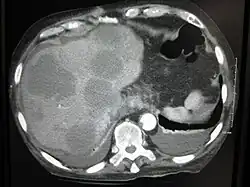

Eine Lebermetastase oder Leberfilia ist eine bösartige Tumorabsiedlung (Metastase, Tochtergeschwulst) in der Leber.

Bei einer Lebermetastase handelt es sich nicht um einen Tumor, der aus den Leberzellen selbst entsteht, sondern es sind Tumorzellverbände anderer Gewebe, die in der Leber hängen bleiben und dort weiterwachsen. Da die Leber durch ihre Kapillargefäße einen Blutfilter darstellt, ist sie relativ häufig von Metastasen betroffen.

Meist finden sich bei genauem Suchen mehrere Metastasen. Einzelmetastasen sind eher selten. Sie lassen sich mittels Ultraschall, CT und MRT darstellen.